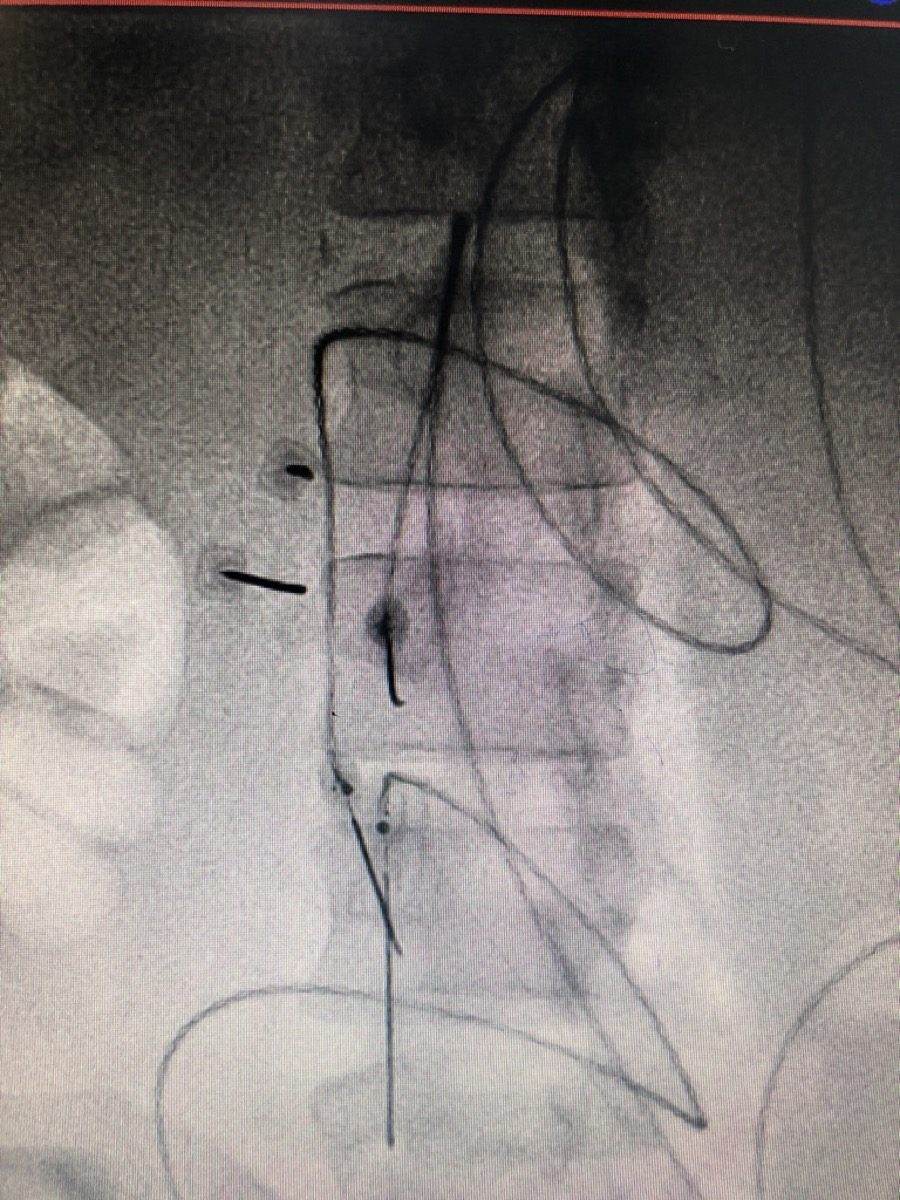

3. MRI or ultrasound of the stump to identify neuromas or other structural causes

4. Diagnostic nerve block to test whether peripheral nerve activity is driving the pain

• Spinal Cord Stimulation (SCS) to modulate the abnormal central pain signals that drive phantom limb pain, providing long-term relief without medication dependence

• Stump Neuroma Injection and RFA to diagnose and treat painful neuromas in the residual limb, reducing the abnormal peripheral signal that feeds into phantom pain

• Dorsal Root Ganglion (DRG) Stimulation for precise targeting of specific nerves supplying the residual limb, particularly useful for lower limb amputees